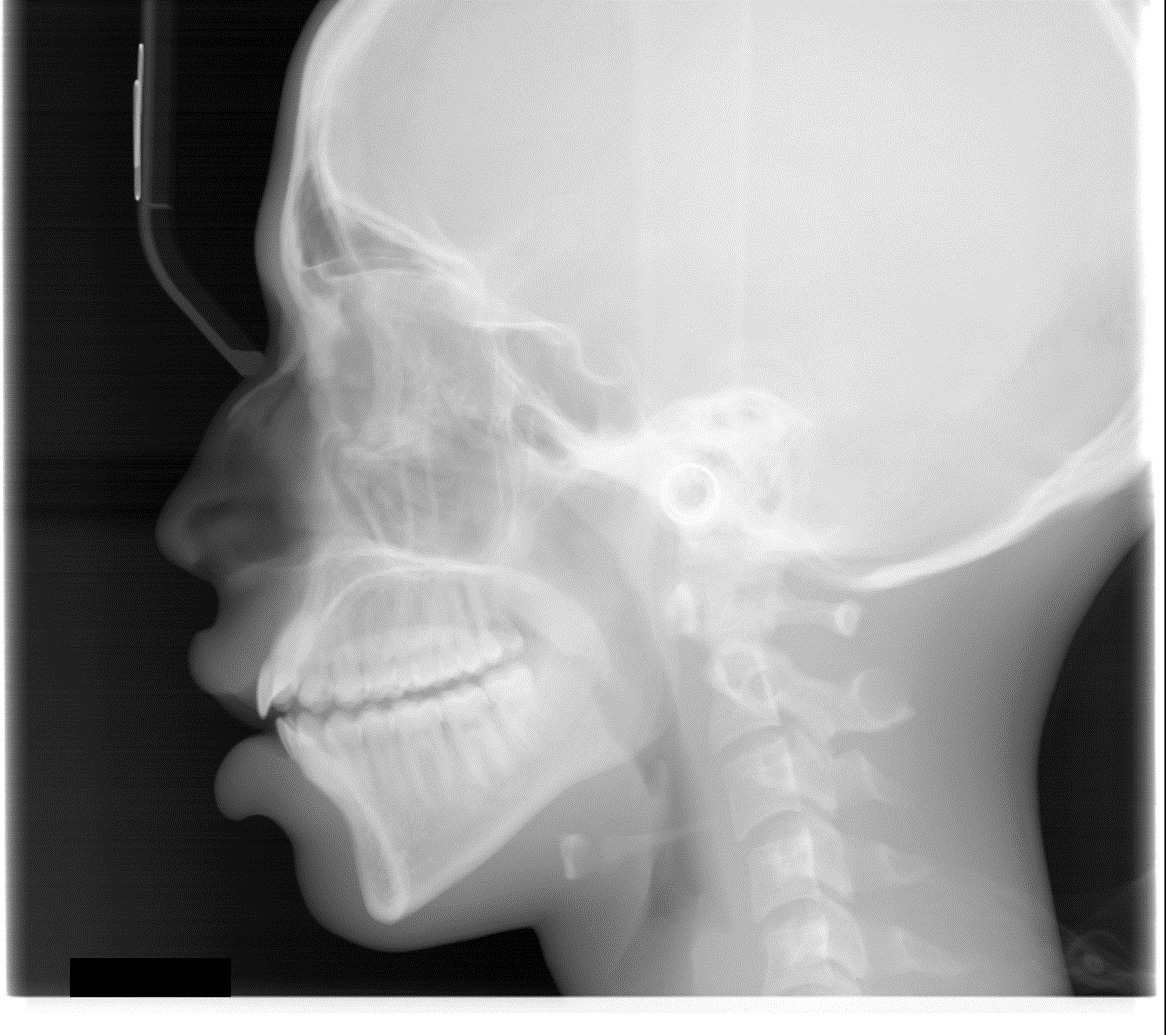

Panoura 18S Images